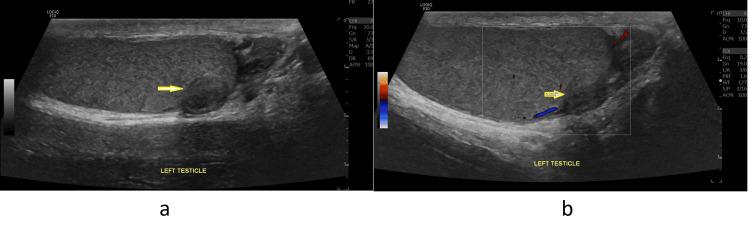

睾丸腺瘤样瘤:两例报告及文献复习

Testicular adenomatoid tumor is a rare benign condition that can resemble testicular malignancies in its clinical presentation, potentially leading to overtreatment, such as radical orchidectomy. In our two case reports, we aim to better understand the behavior of this disease by examining its clinical presentation, as well as radiological, intraoperative, and pathological findings.

睾丸腺瘤样瘤是一种罕见的良性疾病,其临床表现可能类似于睾丸恶性肿瘤,可能导致过度治疗,如根治性睾丸切除术。在我们的两个病例报告中,我们旨在通过检查其临床表现以及影像学、术中及病理检查结果,更好地了解这种疾病的特点。